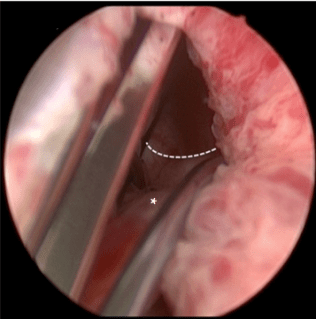

El TIND es un dispositivo de reciente comercialización que se implanta de manera segura y eficaz en el cuello de la vejiga y en la uretra prostática bajo una sedación suave y de manera ambulatoria.

Su diseño le permite expandirse una vez colocado, ejerciendo una fuerza radial hacia el exterior lo que apertura la uretra prostática obstructiva. Una vez implantado, el dispositivo se mantiene colocado durante 5 días. Posteriormente el dispositivo es removido de manera ambulatoria mediante cistoscopia.

La fuerza radial ejercida por el dispositivo en la próstata comprometida, induce una necrosis isquémica que finaliza con la incisión inadvertida de dicha zona.